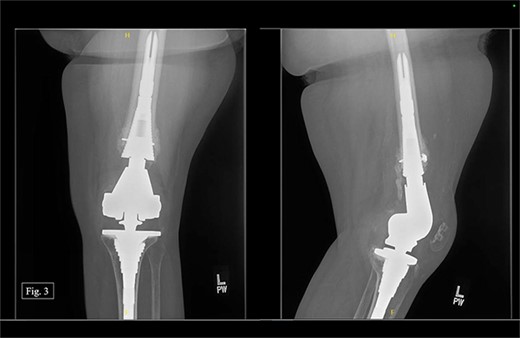

After being discharged from the University Medical Center, the patient visited Texas Tech Orthopedic Clinic 2 weeks after the operation. In July 2020, around 5 months after the operation, she stated that she was regularly and consistently doing physical therapy and reported a pain score of 4/10. During the visit, APand lateral left knee X-rays were taken (Fig. 3).